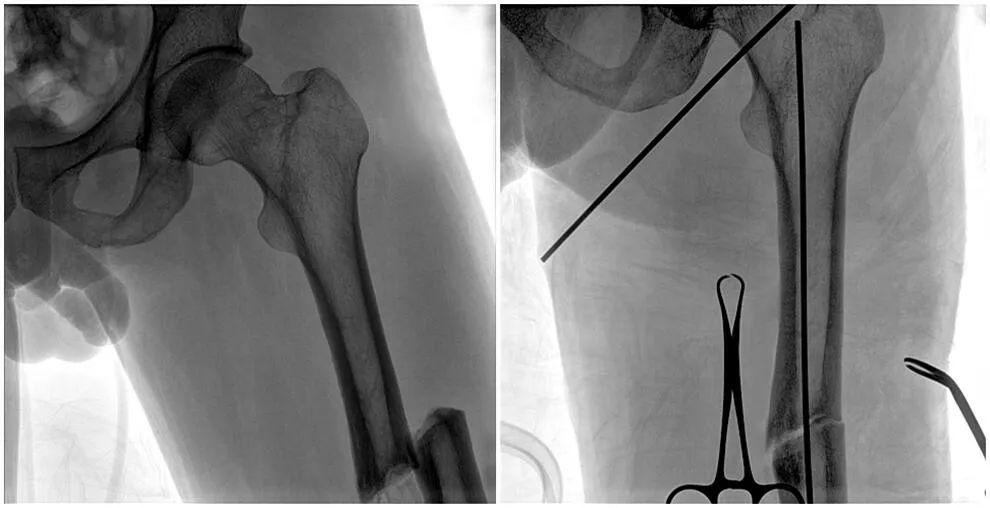

C形臂輔助手術過程

術中使用普愛醫療大平板一體式C形臂進行透視,判斷骨折情況及克氏針、髓內釘等金屬植入物的位置,進行調整。C形臂準確的術中定位,大大縮短了手術的時間,減輕了患者的痛苦,輔助手術順利完成。

在進行髓內釘內固定術時,醫生需要同時觀察到入釘點和骨折部位的情況,普愛醫療大平板一體式C形臂采用30CM×30CM的平板探測器,能夠呈現更廣闊的成像面積,滿足大部分長骨髓內釘內固定術的攝片需求。

術中定位準確、出血量少,術后影像顯示股骨移位糾正,恢復良好力線,手術效果良好。